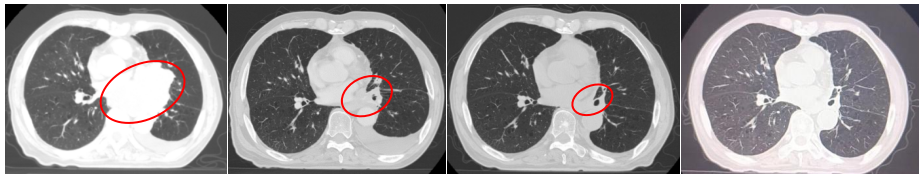

2022-07-19(2周期后)胸部、全腹部增强CT:1.肺癌复查,较前(2022-05-23)左肺门占位明显减小,左肺下叶远端阻塞性改变较前范围减小;2.双肺肺气肿;3.左侧胸腔积液,累及左侧胸膜可能,较前略增多;4.心包少量积液,较前增多;5.肝内多发囊肿;右肾上极小囊肿;6.肝左叶内小海绵状血管瘤可能;7.前列腺增大伴钙化。

2022-09-30(4周期后)胸部、全腹部增强CT:1.肺癌复查,较前(2022-07-19)左肺门占位减小,左肺下叶远端阻塞性改变较前范围减小;2.双肺肺气肿;3.左侧胸腔积液,累及左侧胸膜可能,较前减少;4.心包少量积液,大致同前;5.肝内多发囊肿;右肾上级小囊肿;6.肝左叶内小海绵状血管瘤可能;7.前列腺增大伴钙化。

2022-11-21(6周期后)胸部、全腹部增强CT:左肺门占位较前(2022-09-30)减小,左肺下叶远端阻塞性改变较前变化不大;左侧胸腔积液,累及左侧胸膜可能,较前减少;心包少量积液,大致同前。

疗效评估:PR(接近CR)。